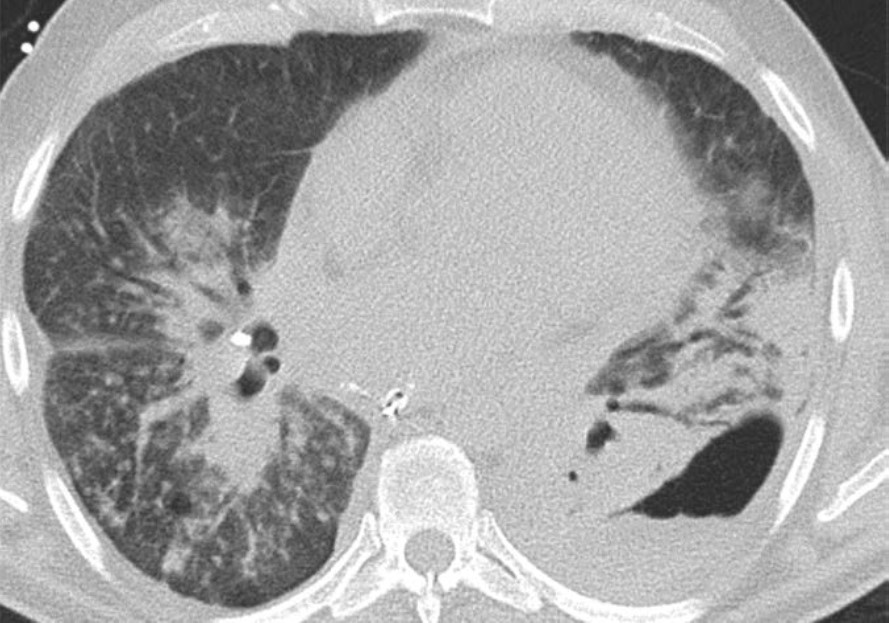

Acute rejection can occur anytime after lung transplant. It consists of two types, acute cellular rejection (ACR) and antibody-mediated rejection (AMR), which can coexist. ACR is the more common of the two types and occurs when recipient T lymphocytes attack donor antigens within the lung allograft. Approximately 35% of lung transplant recipients experience at least one episode of ACR during the 1st year after transplant [2]. During these episodes, patients may be asymptomatic or may present with nonspecific symptoms such as dyspnea and cough. The imaging findings of ACR are nonspecific and include consolidation, ground-glass opacities, and septal-line thickening; as with hyperacute rejection, ACR resembles pulmonary edema. Given its nonspecific clinical and imaging manifestations, ACR requires transbronchial biopsy and tissue analysis for diagnosis. Timely treatment, typically by increased immunosuppression with steroids, is important because ACR is the greatest risk factor for chronic lung allograft dysfunction [4]. Figure 1 shows a patient with biopsy-proven ACR.

AMR, the less common of the two types of acute rejection, occurs when recipient B lymphocytes create donor-specific antibodies (DSA), donor-specific antigens and DSA form complexes, and the complexes trigger the immune system’s complement pathway. Like patients with ACR, patients with AMR can be asymptomatic; can have nonspecific symptoms such as dyspnea and cough; and can have normal chest imaging or nonspecific imaging findings resembling pulmonary edema such as consolidation, ground-glass opacities, and septal-line thickening. Transplant physicians diagnose patients with clinical versus subclinical AMR and definite versus probable versus possible AMR on the basis of the presence or absence of allograft dysfunction, histology results suggestive of AMR (such as neutrophil arteritis and capillaritis), immunostaining results (positive C4d staining of the capillary endothelium), and the presence or absence of DSA in peripheral blood [4]. Treatments include plasmapheresis and IV immunoglobulin to remove harmful antibodies and to suppress antibody production, respectively. Steroids are not typically used to treat AMR, unlike ACR. Figure 2 shows a patient with AMR.

Fig. 2—Patient with history of bilateral lung transplant who developed antibody-mediated rejection (AMR), which was diagnosed by transbronchial biopsy and donor-specific antibody blood testing. Chest CT at time of AMR diagnosis shows ground-glass opacities and reticulation in both lungs and small pleural effusions.